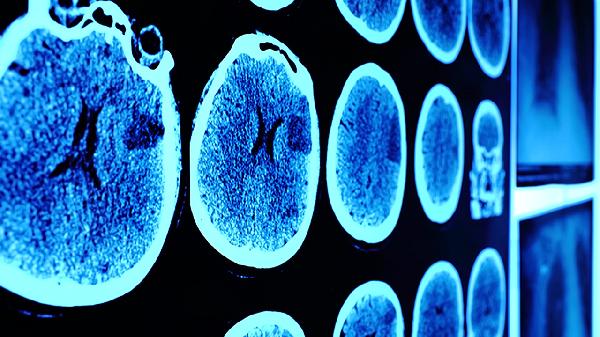

头部遭受钝器打击或剧烈摇晃可导致弥漫性轴索损伤。暴力伤害后可能出现癫痫发作或肢体瘫痪,需立即进行CT检查排除颅内结构性损伤。